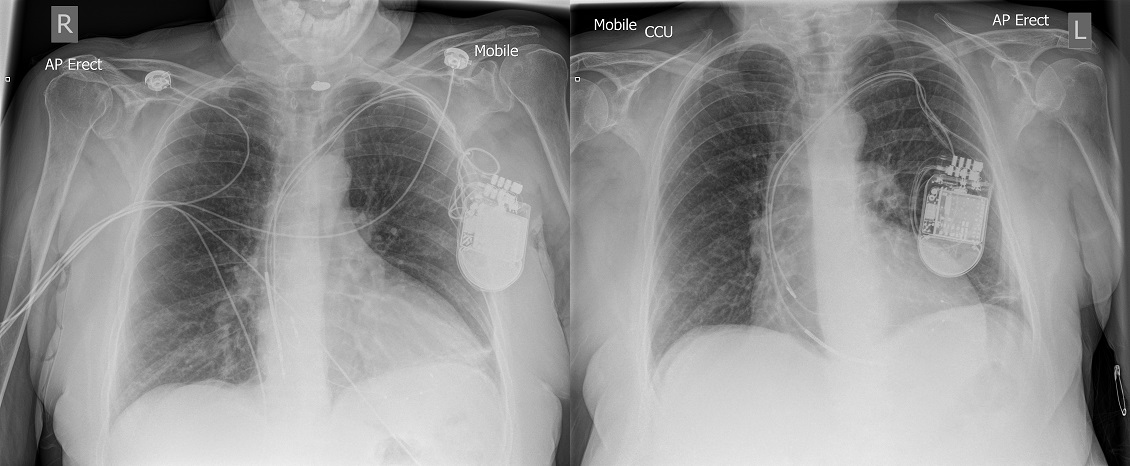

Figure 3

X-ray performed in A&E on the left. Post implant X-ray on the right.

CXR on the left shows ventricular lead displacement in comparison to the post implant CXR. The cause of the ventricular lead displacement is due to Twiddler’s Syndrome which can be seen by the presentation of the leads in the device pocket. The next day the patient underwent urgent right ventricular lead replacement and has since then remained event free.